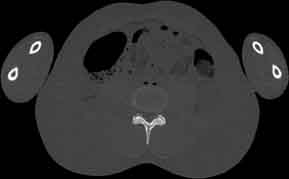

Visible Human male: Sectio transversalis 1728

CT

NMR

Pd                          / T2 \                         T1